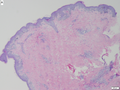

Layers of the skin

- Epidermis - outer most layer, avascular, separated from dermis by a basement membrane, epithelial tissue.

- Dermis - below the epidermis, vascular, separated from the epidermis by a basement membrane, connective tissue.

- The layer below the skin is the subdermis (AKA hypodermis, AKA subcutaneous tissue).

- It is below the dermis and consists of adipose tissue.[3]

Image: